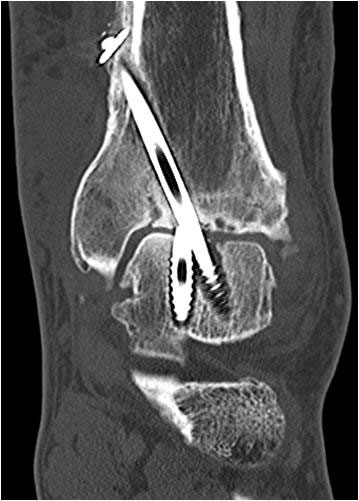

• Primäre oder posttraumatische Arthrose des OSG und USG (Abbildung 1, Abbildung 2).

• Revision einer gescheiterten Fusion des OSG/ USG (Abbildung 3, Abbildung 4).

• Pseudarthrosen (Abbildung 5, Abbildung 6).